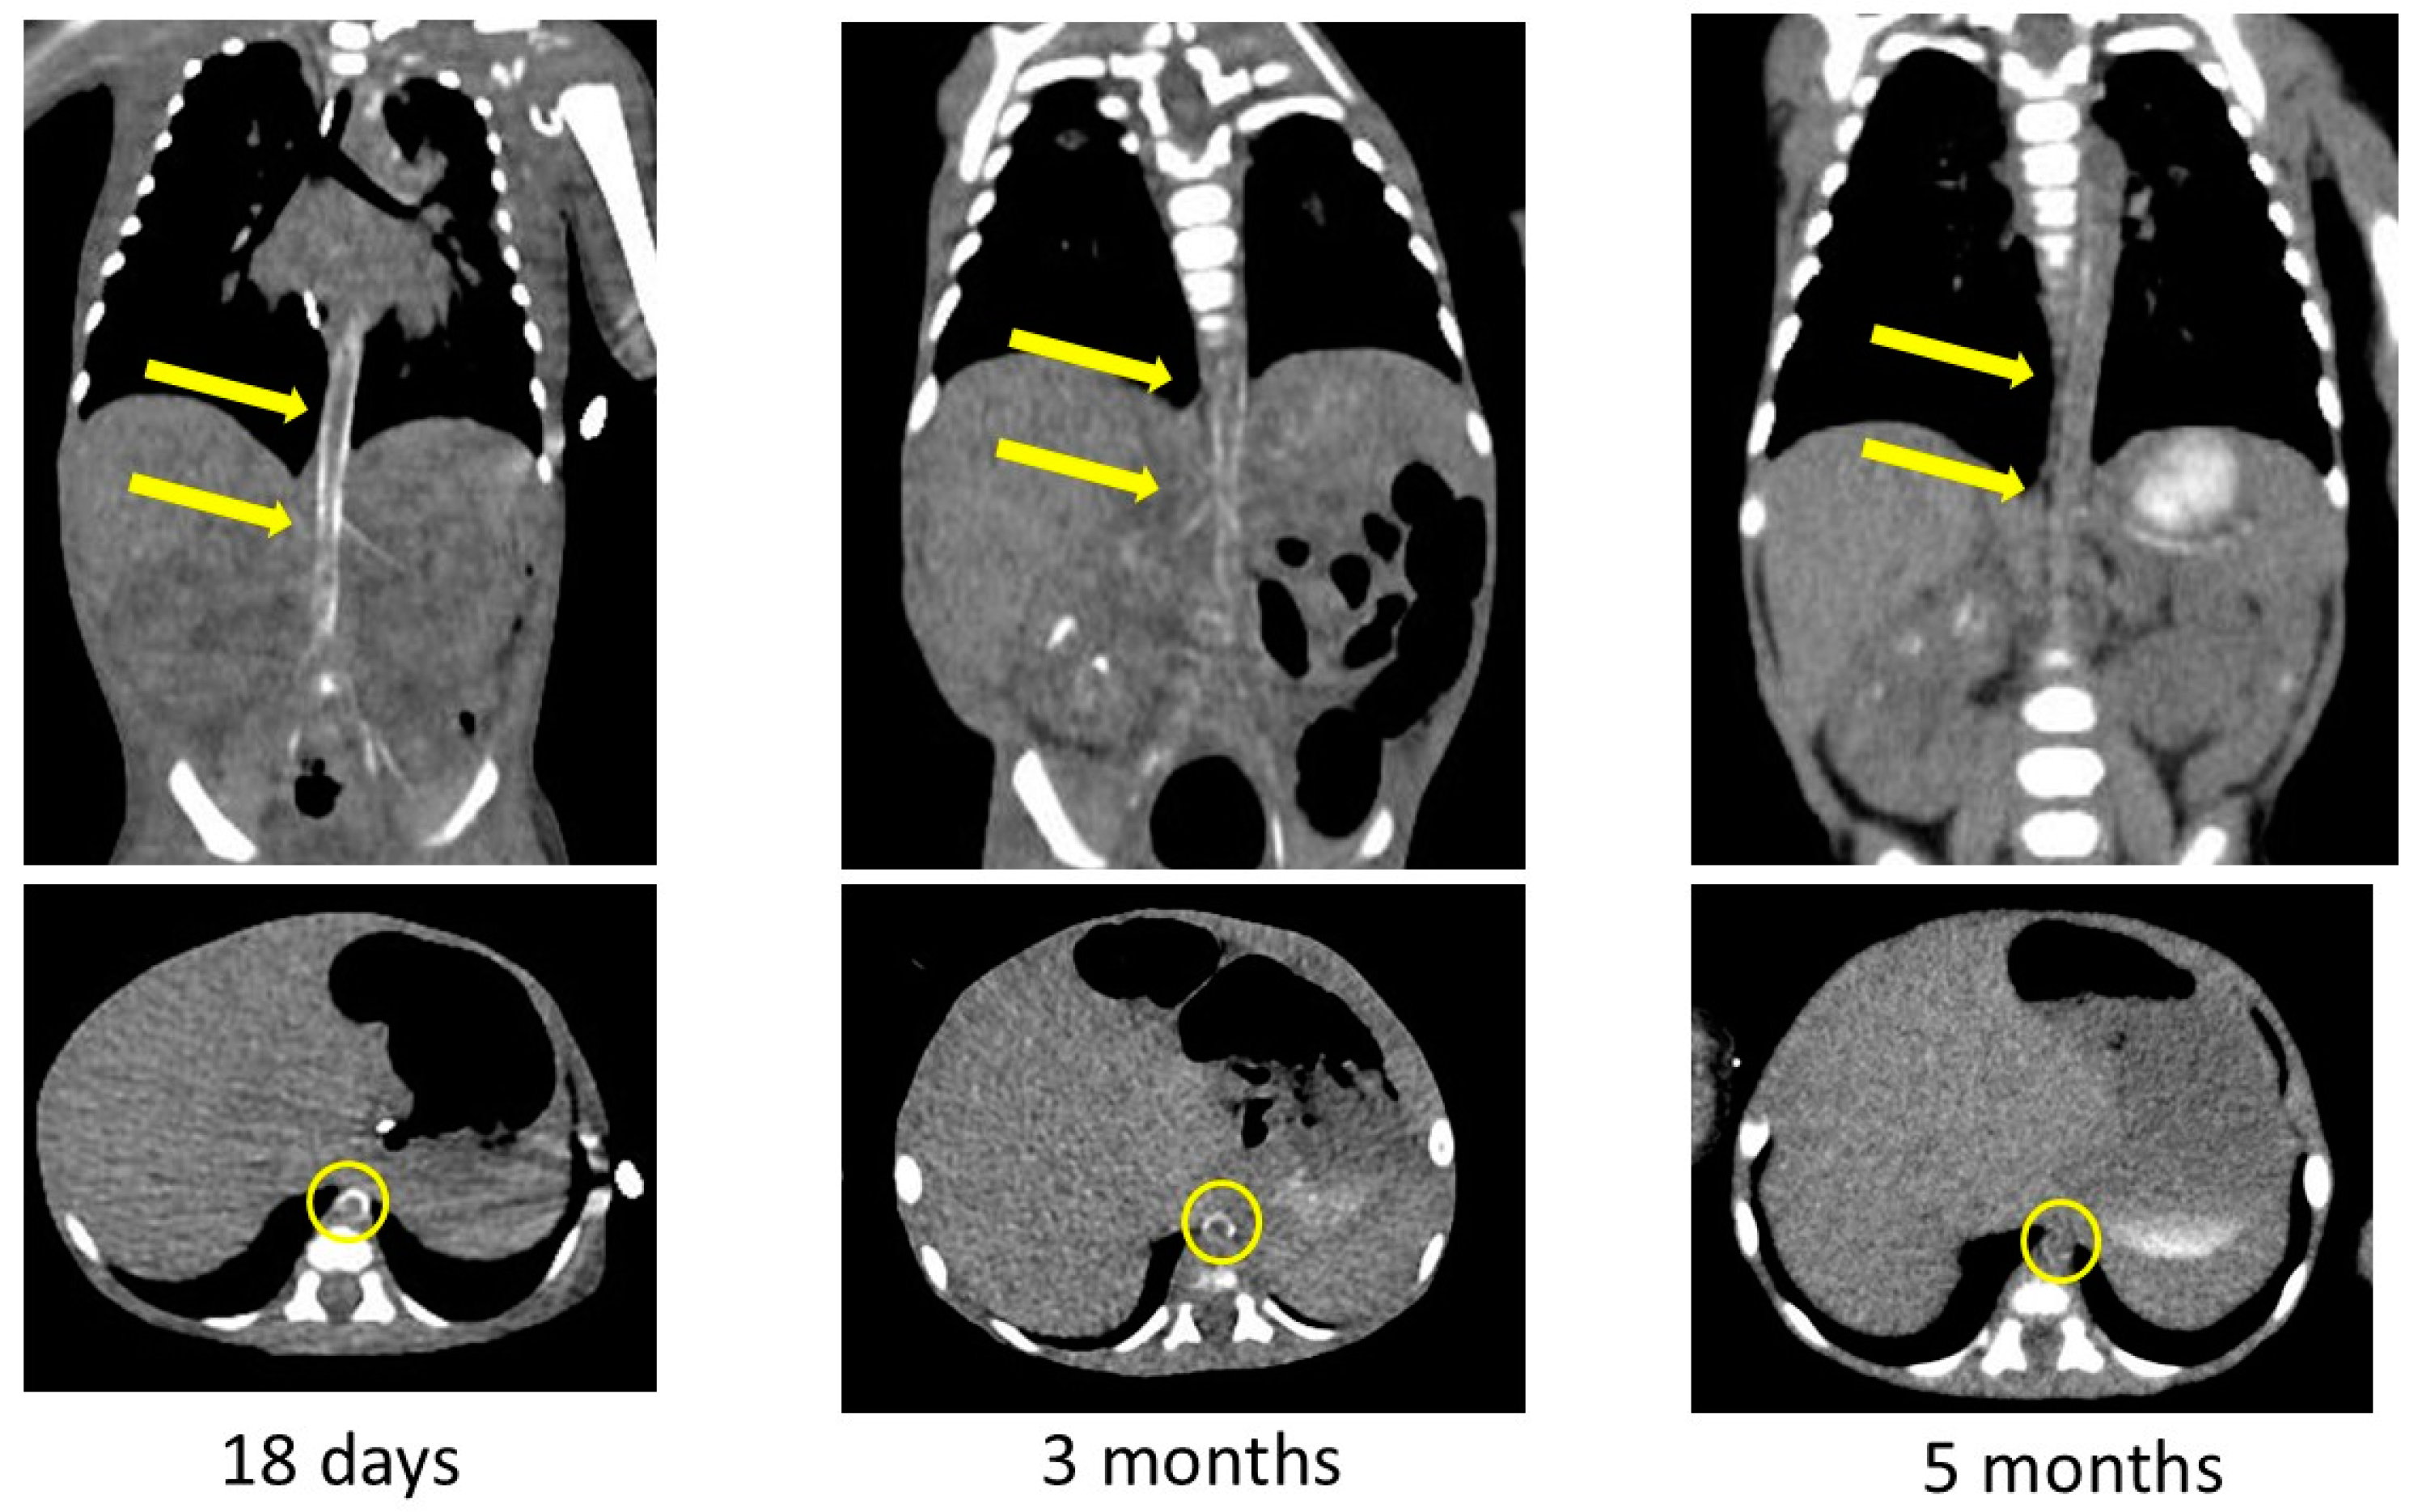

The arterial calcification was decreased on CT images obtained at 3 and 5 months after birth (Figure 5). We had observed high-intensity lesions of the arterial wall by ultrasonography, which began to lighten around 3 months of age and were virtually unnoticeable at 5 months of age, as well as CT images. She was discharged to home 6 months after birth on diuretics, aspirin, antihypertensive medications, and etidronate medications. We performed a hearing test with automated auditory brainstem response, and no hearing loss was found. She was examined by a retina specialist, and her retinal findings were normal.

Figure 5.

Contrast-enhanced computed tomography images showing decreased calcification of the arteries after bisphosphonate treatment. Yellow arrows and circles indicate improvement in arterial wall calcification in the same area.